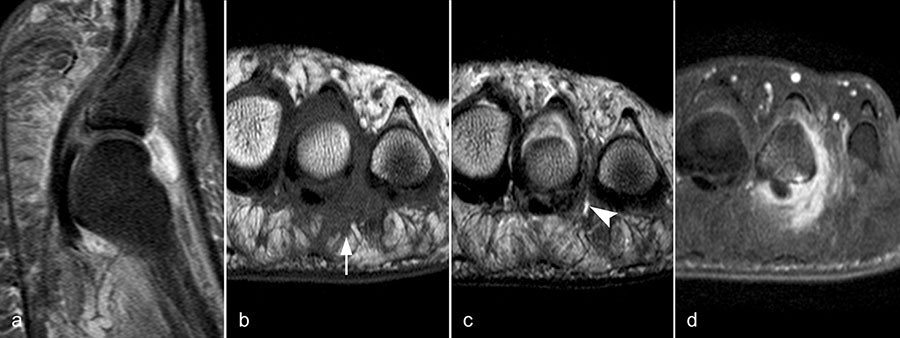

Zwischen der plantaren Platte und der Grundphalanx ist in der Mittellinie des Gelenkes ein kleiner Rezessus vorhanden (Abb. 9).

Dieser flüssigkeitsgefüllte Raum darf nicht als Ruptur der plantaren Platte fehlinterpretiert werden 23. Verletzungen der plantaren Platte erfassen immer auch den medialen oder lateralen Zügel.

Die sagittalen PD FS Schichten im medialen und lateralen Bereich der plantaren Platte (a, c) zeigen eine völlig unauffällige,  Der kleine Flüssigkeitseinschluss in der Mittellinie der Zehe (b, Pfeil) entspricht einem physiolo